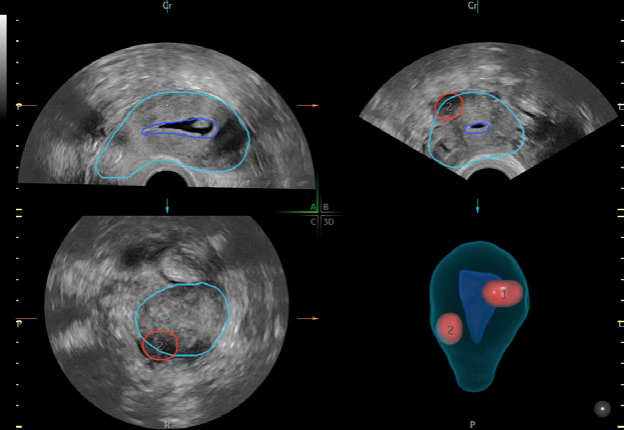

• SonoAVCTM & Auto Caliper measurements for follicles

• SonoGYN with Fibroid Mapping